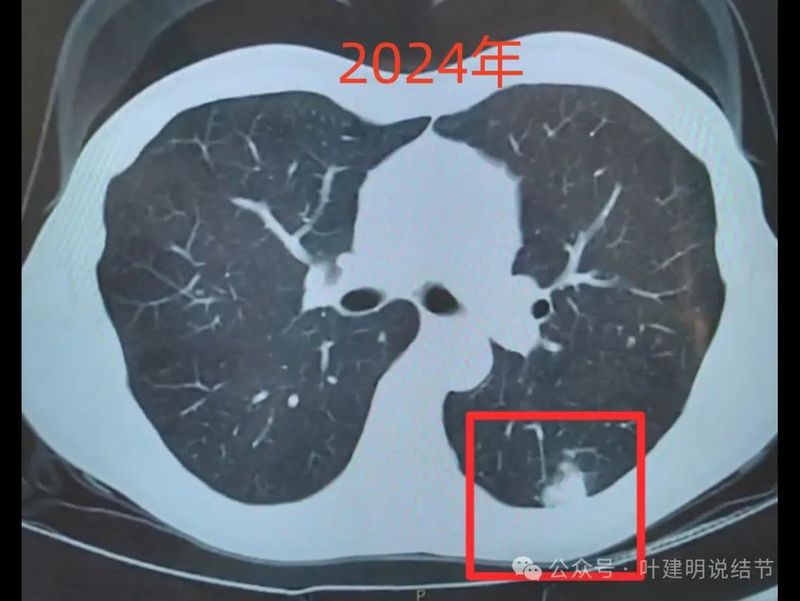

2024年左下病灶团块状,边缘显糊,收缩力不明显。

绿色的是今年与去年基本没有明显变化的,而且多中心,斑点状,考虑是慢性炎可能性大;粉色的右侧的是磨玻璃密度,对比持续存在,轮廓与边界清楚,这个要考虑肿瘤范畴的,但以原位癌可能性较大,目前风险仍不高,能随访;红色的是主病灶,今年发现的,但去年的影像上没有,新发现的这种形态上,首先要考虑是炎性的,至少不能先马上考虑恶性。我的想法是先抗炎治疗10-12天,然后过4周左右复查平扫CT,如果有吸收好转,当然证明是炎性的。如果没有好转,并有进展再来考虑穿刺活检也一样的。穿刺若非肿瘤性,不存在导致转移播散之说,如果穿刺明确是恶性,则接下去就要考虑手术的(如果是原发肺癌),所以也不至于就会因穿刺导致转移而影响预后。当然若抗炎无好转,并高度怀疑恶性,位置在边上,单孔局部楔形切了也是可以的,标本量更够,兼具诊断与治疗双重作用。个人想法考虑良性可能性大,建议先抗炎后复查再决定。意见供参考!

我:等抗炎后复查不好转再考虑回来看,若其实好转了,不是得白跑回来一趟。我觉得不像恶性。恶性能从无到有,发展这么快,那恶性程度要很高,生物学行为就很恶,早个把月开刀也没用。何况影像上也不是那种收缩很强的、恶性程度高的样子。

仅凭影像谁也无法百分之百断定良恶性,但凡是病灶总有个发展过程,总得解释得通,符合其生物学行为才行。若左下此灶真是恶性的,去年没有,今年长这么大,就如我前面说的,那是恶性程度很高的,比如小细胞癌或低分化癌,但真是那样,一是容易发现时就存在微转移,即使早个把月或几个月手术也解决不了问题,预后仍很差;二是那得容易有淋巴结转移呀。而用炎症则各方面更容易解释,所以先别急,稍微缓一缓,或许会有惊喜呢?PET其实并不能做到百分之百,有时炎症它也会报考虑恶性,有时恶性它也会报考虑良性。诊断仍得结合病灶的CT影像特征、发展速度、临床症状,PET表现等综合来评估。